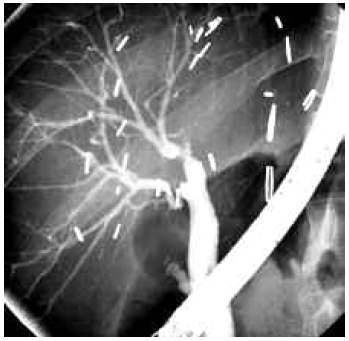

Biliary strictures were usually suspected by elevated levels of bilirubin, alkaline phosphatase, and gamma glutamyl transferase. Strictures also were suspected by finding dilated intrahepatic biliary ducts upon graft imaging. Strictures were confirmed by magnetic resonance cholangiography and later on, by either percutaneous transhepatic cholangiography or by endoscopic retrograde cholangiography (Figure 1). We used the chi-square test to compare categorical variables and the Fisher exact test when necessary. The t test was used to compare means.

Figure 1. Endoscopic retrograde cholangiography showing 2 biliary strictures in a graft with double duct-to-duct anastomosis.